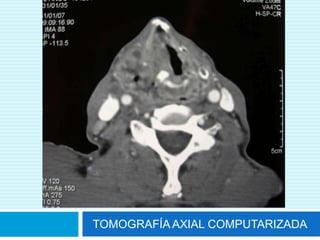

TOMOGRAFÍA AXIAL COMPUTARIZADA